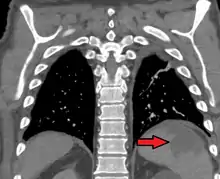

Splenic infarct seen on CT

Several factors may increase the tendency for clot formation, such as specific infections (such as infectious mononucleosis,[9] cytomegalovirus infection,[10] malaria,[11] or babesiosis[12]), inherited clotting disorders (thrombophilia, such as Factor V Leiden, antiphospholipid syndrome), malignancy (such as pancreatic cancer) or metastasis, or a combination[13] of these factors.

In some conditions, blood clots form in one part of the circulatory system and then dislodge and travel to another part of the body, which could include the spleen. These emboligenic disorders include atrial fibrillation, patent foramen ovale, endocarditis or cholesterol embolism.

Splenic infarction is also more common in hematological disorders with associated splenomegaly, such as the myeloproliferative disorders. Other causes of splenomegaly (for example, Gaucher disease or hemoglobinopathies) can also predispose to infarction. Splenic infarction can also result from a sickle cell crisis in patients with sickle cell anemia. Both splenomegaly and a tendency towards clot formation feature in this condition. In sickle cell disease, repeated splenic infarctions lead to a non-functional spleen (autosplenectomy).

Any factor that directly compromises the splenic artery can cause infarction. Examples include abdominal traumas, aortic dissection, torsion of the splenic artery (for example, in wandering spleen) or external compression on the artery by a tumor. It can also be a complication of vascular procedures.[14]